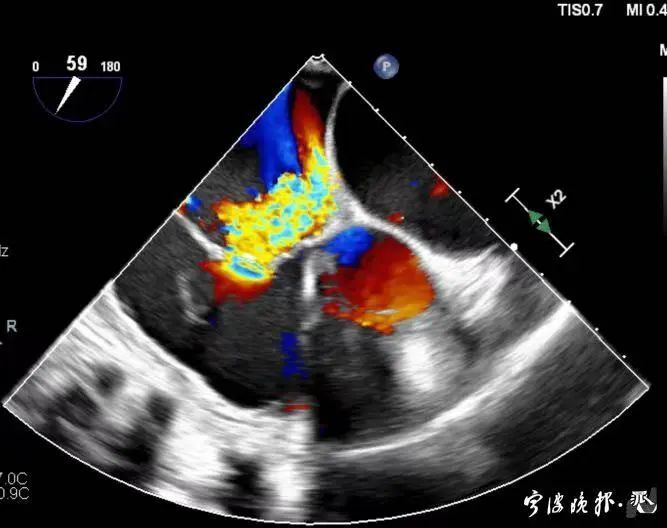

術(shù)前食道心超示三尖瓣重度反流

術(shù)后食道心超示三尖瓣反流消失

得知可以微創(chuàng)手術(shù),陳大爺一家決定放手一搏。寧波市醫(yī)療中心李惠利醫(yī)院心臟瓣膜中心團(tuán)隊(duì)反復(fù)就術(shù)前準(zhǔn)備、手術(shù)步驟及術(shù)后可能出現(xiàn)的各種情況做了預(yù)案。3月4日,陳大爺?shù)氖中g(shù)成功進(jìn)行,術(shù)中得到LuX-Valve經(jīng)導(dǎo)管三尖瓣置換術(shù)原創(chuàng)團(tuán)隊(duì),上海長(zhǎng)海醫(yī)院陸方林主任團(tuán)隊(duì)的鼎力支持,術(shù)后陳大爺?shù)男呐K三尖瓣反流立即消失。術(shù)后瓣膜中心CCU(心臟監(jiān)護(hù))團(tuán)隊(duì)和心內(nèi)科團(tuán)隊(duì)迎接一個(gè)又一個(gè)右心瓣膜置換后的血流動(dòng)力學(xué)改變等帶來的挑戰(zhàn),克服種種難關(guān),二周后患者進(jìn)入早期心臟康復(fù)。目前陳大爺已經(jīng)順利出院,沒有胸悶氣急,生活自理,精神狀態(tài)也很好,瓣膜中心團(tuán)隊(duì)也在對(duì)他持續(xù)隨訪中。